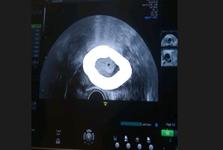

autor@martinka0209 ano to je váček pan doktor potvrdil těhotenství 🥰

autor@makovice88 ne já se nedivím já jsem spíše šťastná ale mě se už jednou stalo že jsem potratila a na ultrazvukové vyšetření nebylo nic proto to píšu takhle že mě moc překvapilo a jsem šťastná že v děloze už jde něco vidět 👌

Já jsem asi debil, ale nějak nechápu, co mám na tom ultrazvuku vidět, nebo kde přesně je problém 🙈.